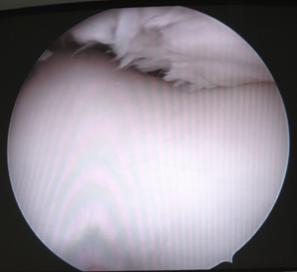

1.3. Diagnosticul Artroscopic al leziunilor cartilajului articular

Examinarea artroscopica a genunchiului ramine standardul de aur in diagnosticarea si evaluarea leziunilor cartilajului articular. Examenul artroscopic permite evaluarea suprafetei cartilajului, a rezistentei la presiune, dar mai ales a marimii si profunzimii zonei leziunii condrale. Numeroase sisteme de clasificare a leziunilor cartilajului articular au la baza examinarea artroscopica directa a acestuia (vezi capitolul 2).

Examinarea artroscopica a cartilajului permite evaluarea mai multor caracteristici ale acestuia. Rezistenta cartilajului la presiune se efectueaza cu ajutorul exploratorului (probe), si se refera la forta cu care acesta este impins inapoi dupa ce presiune a incetat. Persistenta unei depresiuni condrale este semn de "inmuiere" a cartilajului. Artroscopic se evalueaza si culoarea cartilajului care normal este alba, lucioasa, cu usoara tenta galbuie. Cartilajul artrozic are o culoare galbuie marcata, este mat.

La examinarea artroscopica suprafata cartilajului este neteda, lucioasa, o fara discontinuitati. Pierderea luciului, prezenta unor depresiuni, fisuri, fibrilatii, delaminari sint semne de leziune. De asemenea, o zona de ingrosare a cartilajului, depresibila la examinarea cu exploratorul, este semnul unei leziuni profunde: "blister".

Fig. 1.13. Imagini artroscopice - leziuni osteocondrale stadiu III B si C ICRS la nivelul condilului femural si la nivelul patelei |